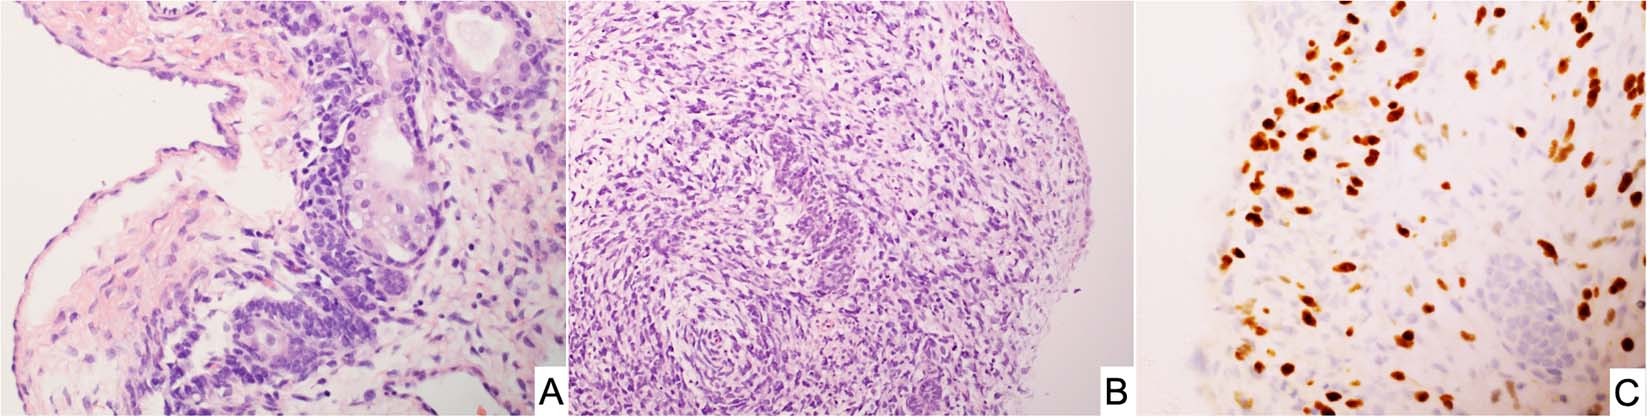

Fig. 8: Sertoli-Leydig cell tumor, moderately differentiated in a 15-year-old female.

A A cystic focus showing a group of Sertoli cells beneath a low cuboidal epithelial surface. B Nests of Sertoli cells surrounded by malignant-appearing, primitive-appearing spindle and round cells in another cystic area of the tumor. C MyoD immunostaining showing intense nuclear positivity to corroborate heterologous rhabdomyosarcoma.